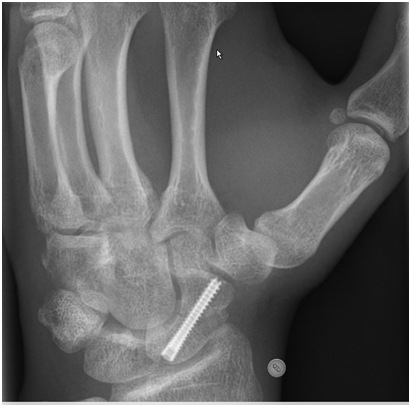

A displaced fracture has a significantly lower union rate and so in these cases surgery may be offered. Surgery is also offered for proximal pole fractures because the blood supply in this region is poor and thence the union rates lower. Surgery will entail a general or a regional anaesthetic (wide awake surgery with numbed arm), and then a screw is passed and buried within the substance of the scaphoid.

There is a period of immobilisation thereafter but less than with non-operative treatment. Surgery has a few risks and does not guarantee union. When patients present late with a scaphoid that has not united then it is often necessary to use bone graft (taken from pelvis or back of wrist) as well as screw fixation. Your surgeon will discuss this with you.